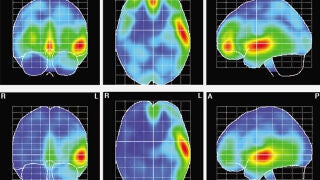

Los resultados, publicados en el Journal of Creative Communications, mostraron que tanto el grupo masculino como el femenino activaron el lóbulo temporal izquierdo. Sin embargo, en ellas también se activó la ínsula izquierda y las áreas orbitofrontales de ambos hemisferios, además de observarse diferencias significativas en sus áreas occipitales del cerebro.

"Nuestros hallazgos evidencian que la escena violenta activó áreas emocionales tanto en el grupo masculino como en el femenino, pero en las mujeres también se produjo una activación de áreas cerebrales relacionadas con el reconocimiento de formas y colores y con procesos cognitivos", señalan los autores.

Su conclusión es que las participantes se enfocaron en esos aspectos emocionales y visoespaciales (colores, formas y detalles) de la secuencia con violencia, mientras que ellos se dejaron llevar únicamente por su contenido emocional.